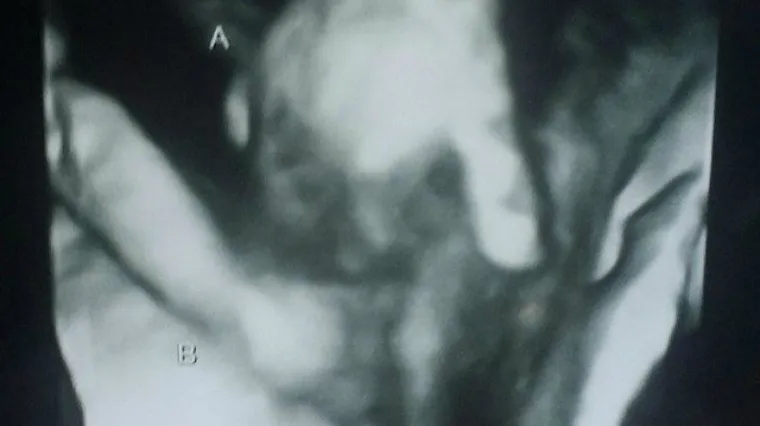

Utješna fotografija s ultrazvuka: dječak koji umire drži svoju sestru blizanku za ruku!

Snimka s ultrazvuka utješila ih je. Na njoj se vidi kako dječak Mason drži za prst svoju sestru Madilyn

Amerikanki Brittani McIntire liječnik je otkrio kako joj jedan od blizanaca koje očekuje umire i njena je tuga bila neopisiva.

Ipak, nakon tog saznanja, utješila ju je fotografija s ultrazvuka na kojoj se vidi kako dječak koji umire drži svoju sestru blizanku za ruku.

Dječak se ne razvija kako treba zbog rupa na srcu i oštećenja na mozgu, a preživio bi samo kad bi operirao srce. No, to ne žele napraviti zbog komplikacija s mozgom.

"Većina blizanaca se, kod ovakvih snimaka, međusobno udara, a rekli su nam da se čini da se naši blizanci ponašaju vrlo zaštitnički", ispričala je Britanni.